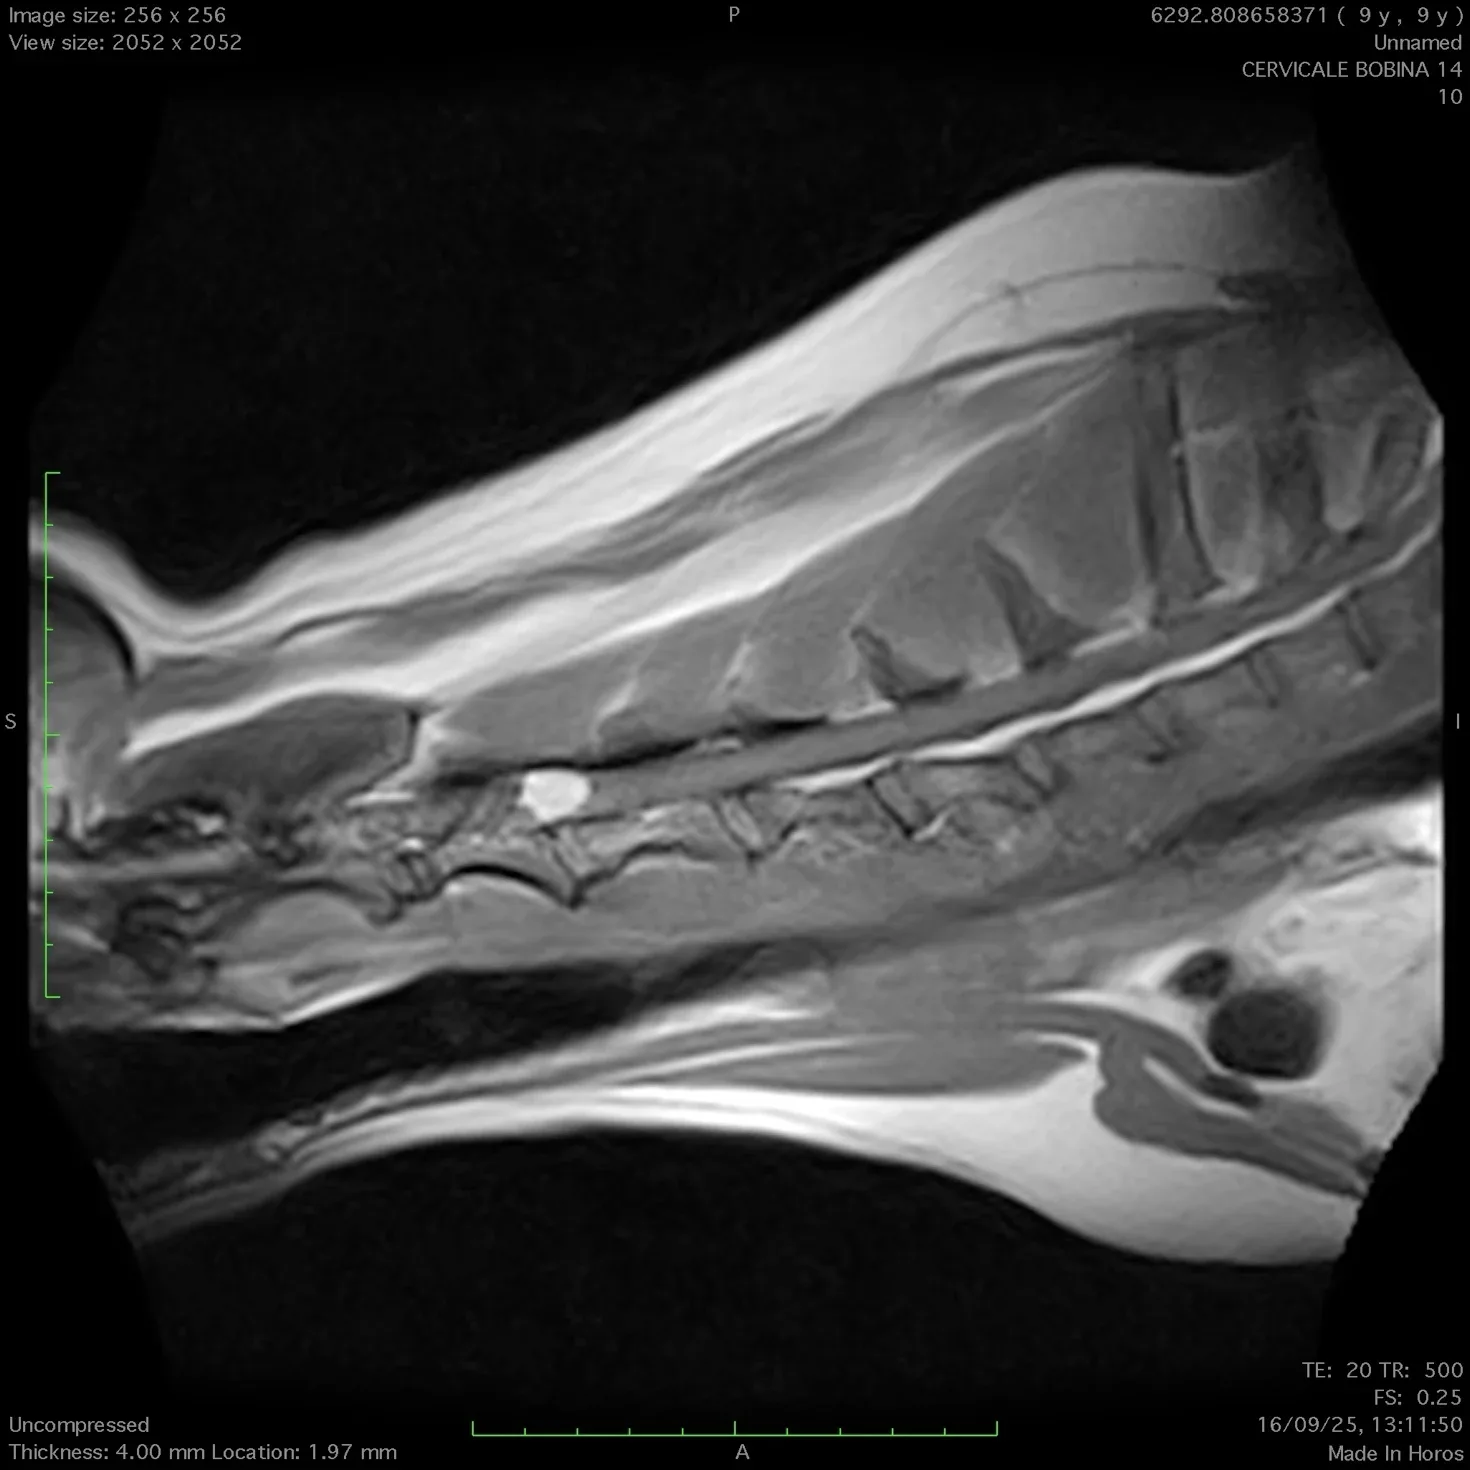

Successivamente alla visita, dopo aver effettuato esami e approfondimenti con ecografie e quanto necessario in genere, per effettuare la diagnosi ,si procede all’esecuzione di  un esame di risonanza magnetica nella sede di interesse ( encefalo o colonna vertebrale).

Con questa procedura chirurgica si eseguono interventi alla colonna vertebrale per la rimozione di ernie del disco che portano alla paralisi degli arti.

In caso di ernie del disco la procedura è molto urgente e se eseguita nei tempi previsti permette la guarigione del paziente nel 98% dei casi.

E’ possibile altresi rimuovere neoplasie esterne al midollo  ( lesioni intradurali o extradurali) ed in taluni casi selezionati  si possono rimuovere neoplasie encefaliche (meningiomi) .